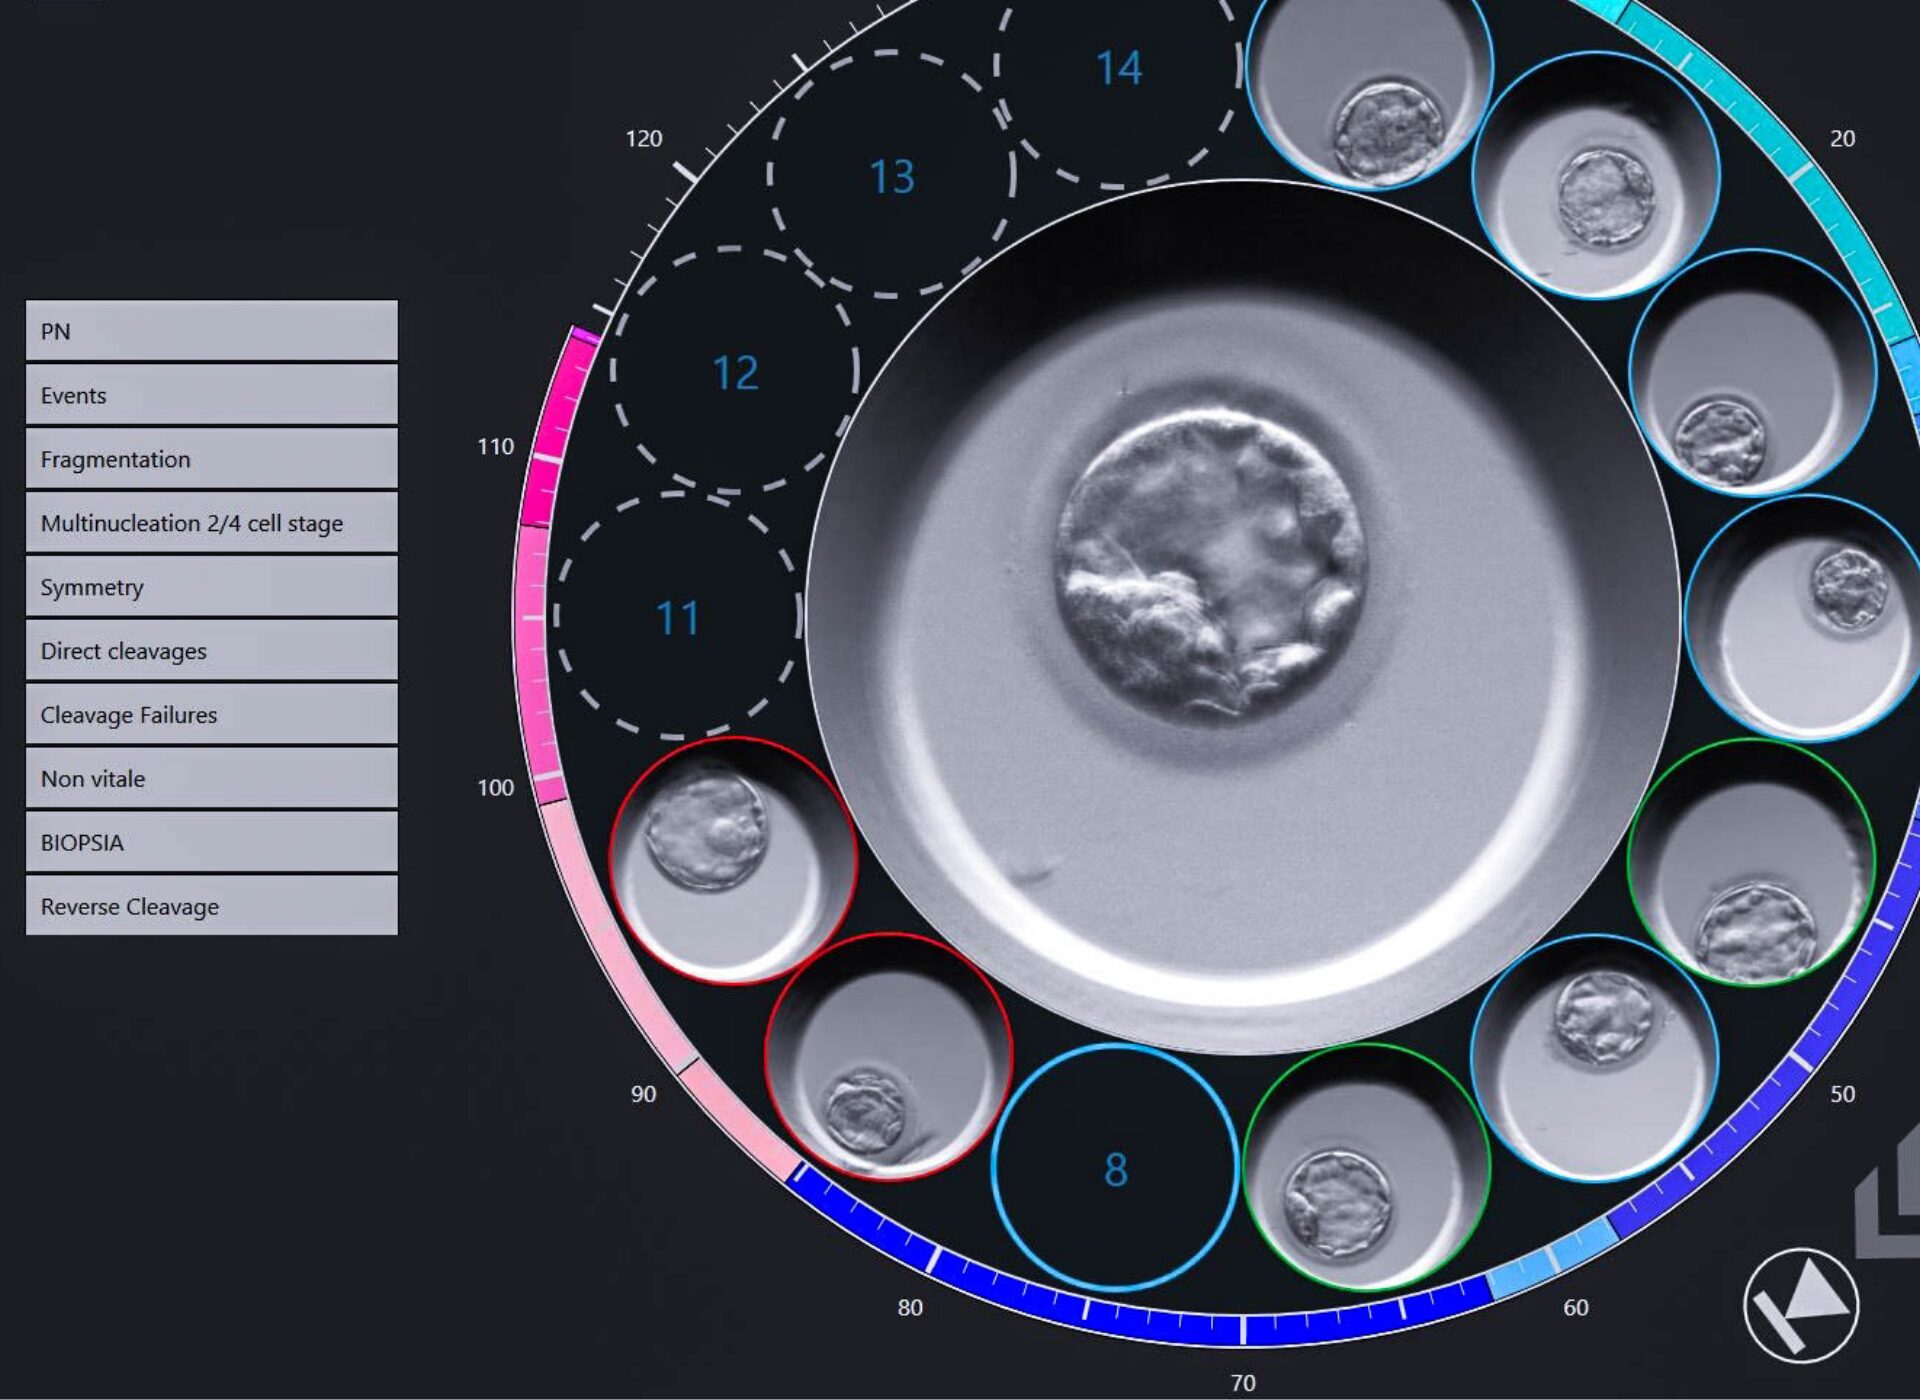

Sempre con Te

Comunicazione diretta tra la coppia e il laboratorio:

Ti raccontiamo come stanno crescendo i tuoi piccoli embrioni passo dopo passo.

Eccellenza Certificata

Tutte le nostre embriologhe sono certificate ESHRE, sinonimo di qualità e competenza.